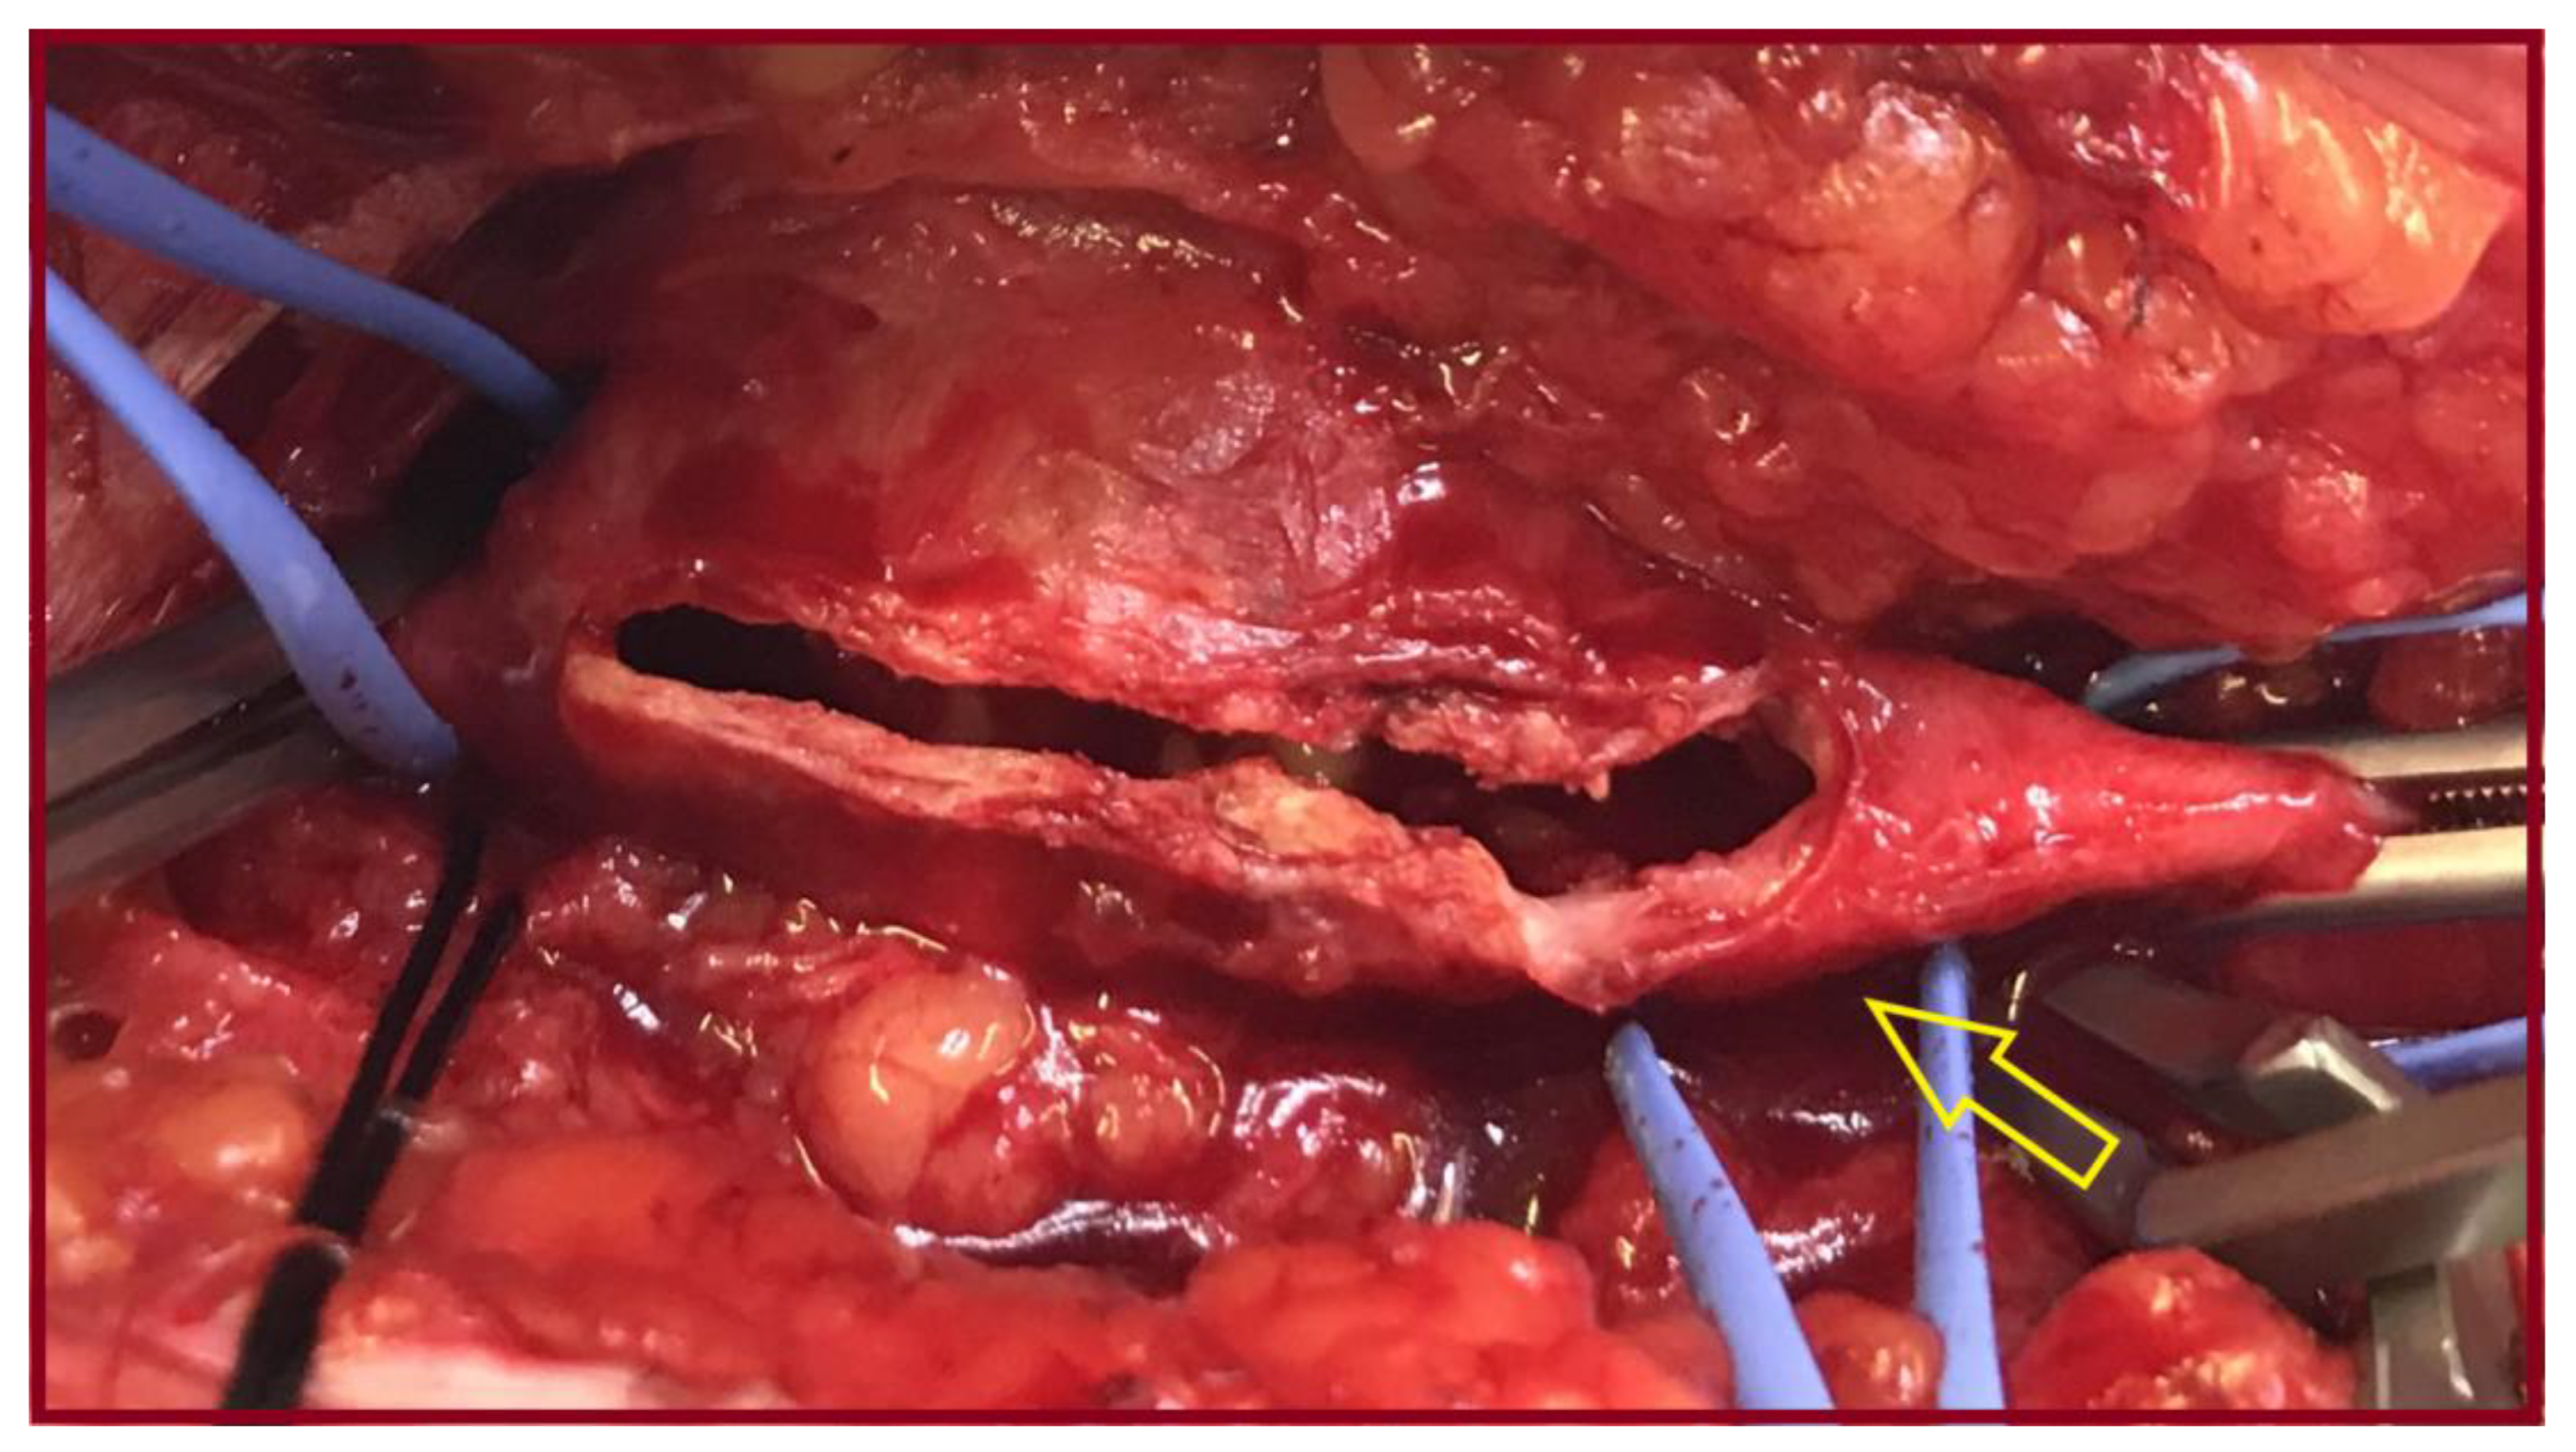

3.1. Case 1

3.2. Case 2

3.3. Case 3